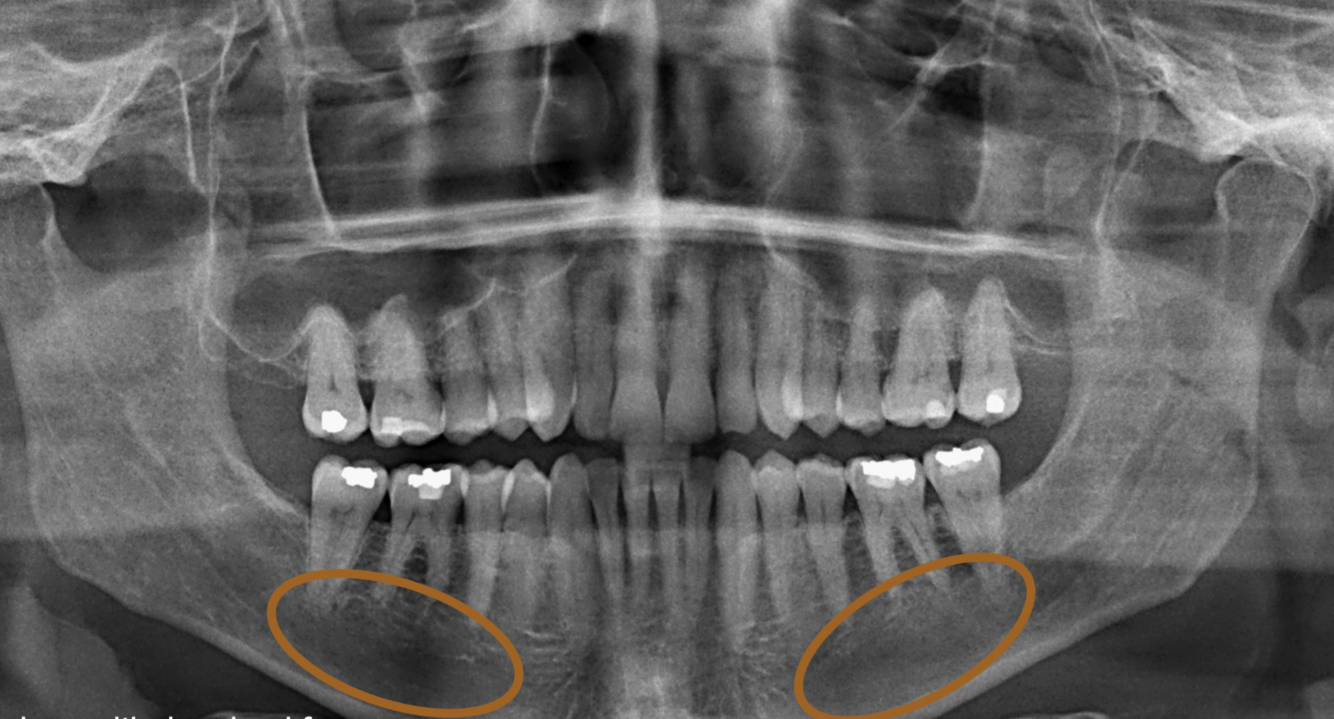

What is circled in the following image?

External auditory meatus

33

What is indicated by the red circles in the following image?